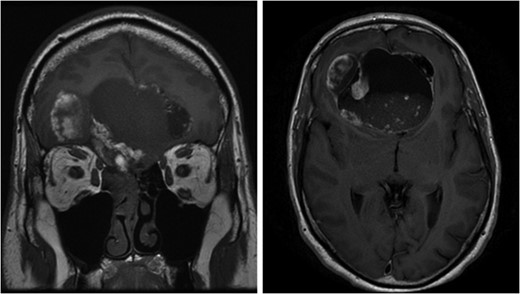

CT and MR imaging revealed a large soft tissue mass extending from his right nasal cavity and ethmoid sinus through the anterior skull base with erosion of bony walls and infiltrating into the frontal lobe causing significant mass effect (Fig. 1). The intra-axial section of the lesion had a large cystic component which appeared to contain sediment material. His case was discussed at the local multi-disciplinary team. The consensus decided against an initial transnasal biopsy as there was significant intracranial mass effect and brain shift. A direct combined neuronavigation guided transcranial (bifrontal) and endonasal approach was planned and performed. Intraoperatively it became apparent that the right olfactory bulb was missing whilst the left remained intact, initially suggesting a neuroectodermal origin. Although it affected predominantly the frontal lobe, it extended posteriorly and was infiltrating the hypothalamus. As such complete excision was not possible as during debulking of this posterior aspect of the tumour the measured urine output increased to 300 ml in 15 min.

Left image: Coronal pre-operative T1 weighted MRI scan showing extension of the lesion from right nasal cavity to frontal lobe. Right image: Axial pre-operative T1 weighted MRI scan with contrast demonstrates the cystic compartment and mass effect of the lesion.